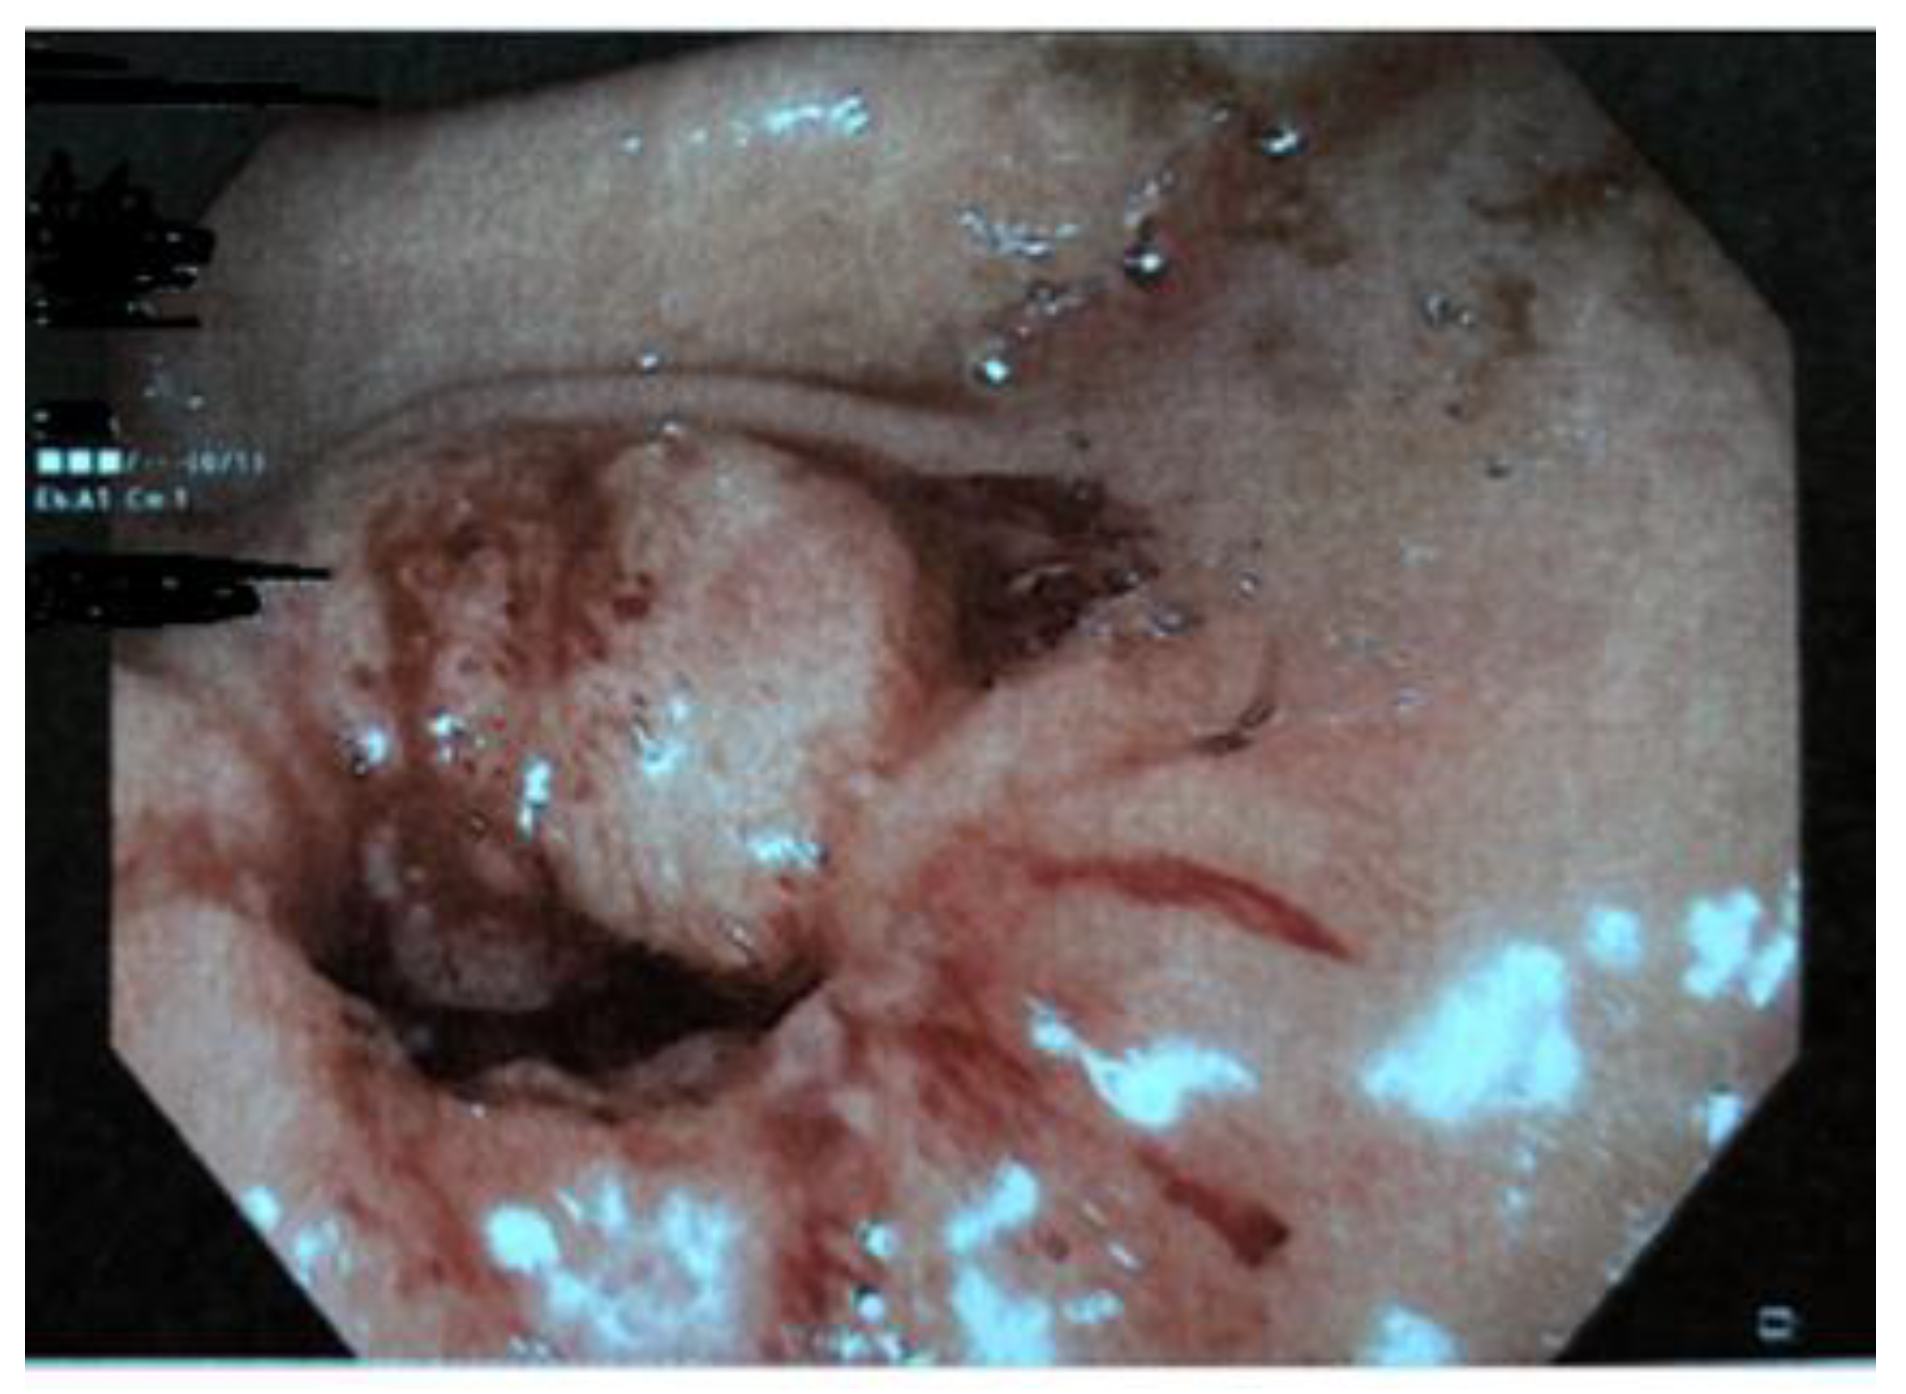

| Boybeyi et al. [16], 2010 | 11 | 3,6 (2–8) years (mean age, range) | Vomiting (5 cases) Vomiting + abdominal pain (4 cases) Vomiting + weight loss (2 cases) | US + UGI series (6 cases), UGI series (5 cases), EGDS | Gastric edema and hyperemia (2 cases) | EBD (4 cases)–EBD + B-I (1 case)–B-I (6 cases) |

| Parnall et al. [7], 2016 | 1 | 15 years | Vomiting, early satiety, failure to thrive | US, CT | Prepyloric ulcer (Hp positive) | Botulinum toxin injection (failure), distal gastrectomy with Billroth I reconstruction |

| Wolf et al. [8], 2016 | 1 | 17 years | Abdominal pain, bloating, early satiety, one episode of upper gastrointestinal hemorrage, anemia | EGDS (2), MRI enterography, gastric emptying study using Technetium-99 | Severe gastritis | Botulinum injection (failure), LP |

| Bartlett et al. [19], 2018 | 1 | 12 years | Vomiting, failure to thrive | EGDS, US. | Previous history of eosinophilic esophagitis. Gastritis. | EBD + Botulinum injection (failure) HMP + temporary gastrostomy |